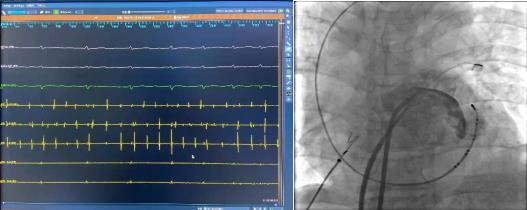

術(shù)前腔內(nèi)電圖可見(jiàn)毫無(wú)規(guī)律的房顫波,接著穿刺房間隔建立左房通路。完成肺靜脈隔離及頂部線(xiàn)消融后房顫轉(zhuǎn)復(fù)為規(guī)律的心房撲動(dòng)。

激動(dòng)標(biāo)測(cè)提示二尖瓣峽部依賴(lài)性房撲,而在消融過(guò)程中發(fā)現(xiàn)患者肌袖比較發(fā)達(dá),進(jìn)行二尖瓣峽部線(xiàn)性消融后不能終止房撲,結(jié)合患者情況決定進(jìn)行Marshall靜脈酒精消融。

冠狀竇造影定位Marshall靜脈,應(yīng)用OTW球囊進(jìn)行酒精消融